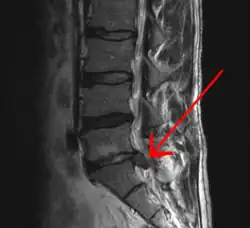

MRI-scan van een lage hernia | ||||

- MRI (kernspintomografie). Dit onderzoek is het onderzoek van eerste keus. In vrijwel alle gevallen zal het mogelijk zijn om hiermee de diagnose hernia te stellen.